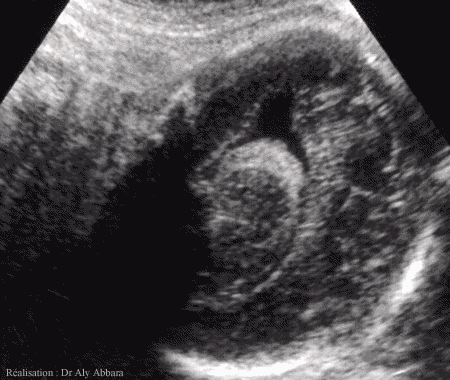

Coupe parasagittale cérébrale fœtale montrant

le ventricule latéral et les plexus choroïdes